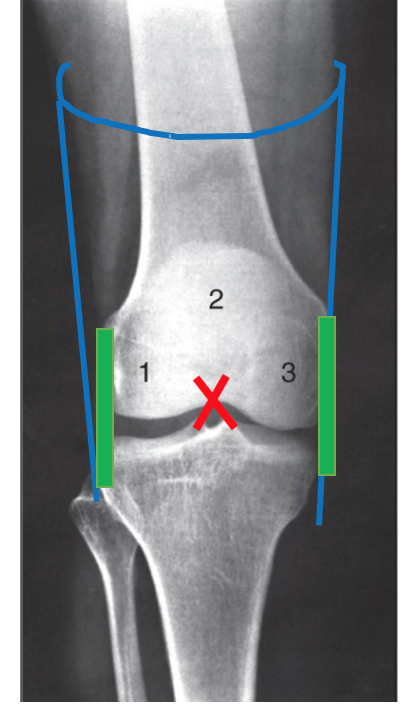

Label the 2 ligaments

What is their main function?

they sit in a crossed fashion inside the joint and prevent lateral displacement of the femur and tibia

What is the origin and attachment of the posterior cruciate ligament?

it attaches to the posterior intercondylar region of the tibia

it travels supero-anteriorly to insert onto the medial femoral condyle

What is the attachment and insertion of the anterior cruciate ligament?

it attaches to the anterior intercondylar region of the tibia

it travels supero-posteriorly to attach to the lateral femoral condyle

Which cruciate ligament is stronger?

the posterior cruciate ligament is STRONGER than the anterior cruciate ligament

Label the cruciate ligaments as if looking down inside a left knee